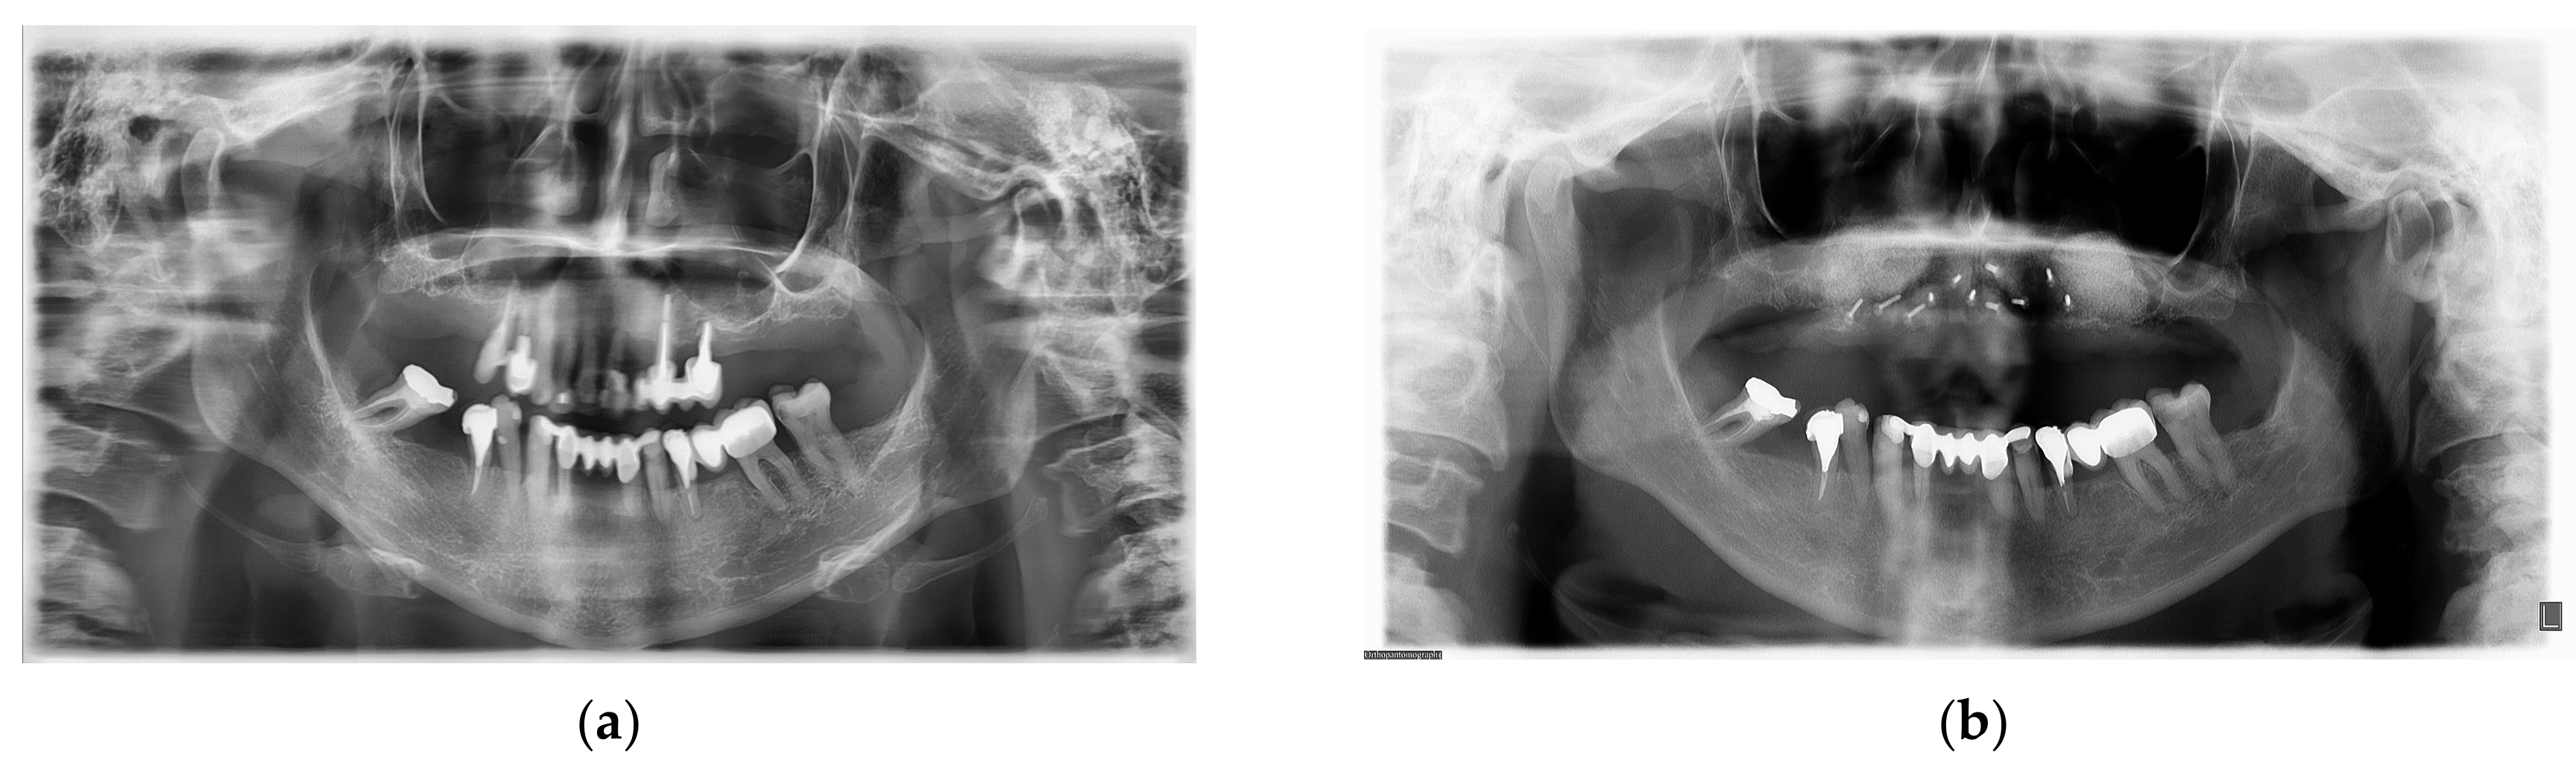

2. Case Report